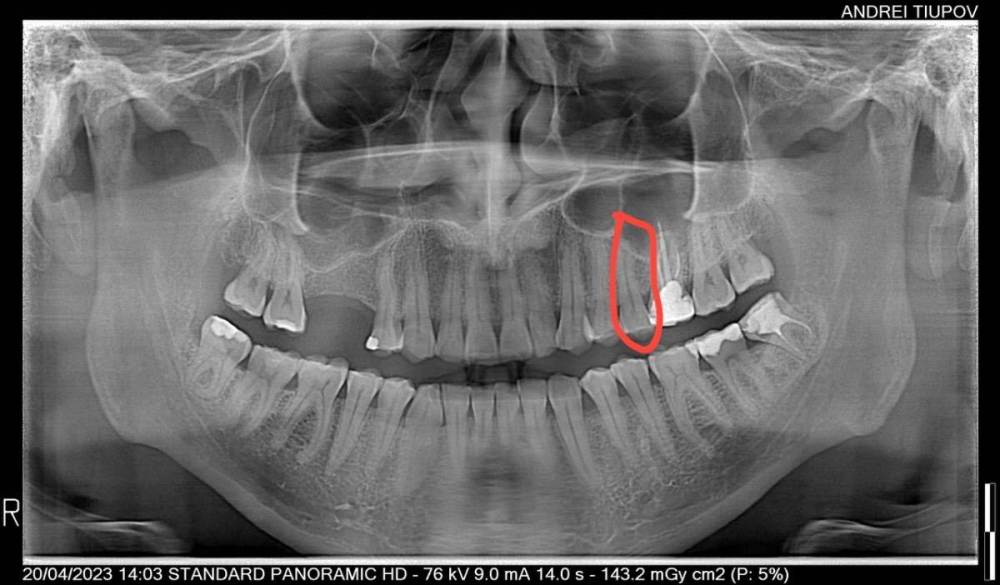

randomsctions Опубликовано 22 апреля, 2023 Автор Поделиться Опубликовано 22 апреля, 2023 Стучали все три врача, но разницы никакой я не заметил. вчера сделали тест: ввели небольшое количество анестетика под каждый зуб с перерывом в 10 мин, чтобы посмотреть, когда утихнет боль. идентифицировали вот этот зуб таким оьразом (оьвёл красным на картинке). Удалили нерв и запломбировали канал. Боль изменилась, но не прошла. Накатывает волнами теперь от почти 0 до 7 по 10-бальной шкале, с периодом около 30 мин +-. Но хотя бы могу спать теперь. Всё ещё буду рад советам, т.к. до сих пор непонятно, в чем проблема. Ссылка на комментарий